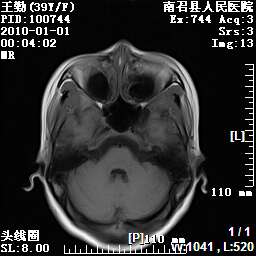

以下是引用随光逐影在2010-1-22 9:03:00的发言:[br]考虑左侧中颅窝(蝶骨翼区)脑膜瘤侵犯蝶骨翼并突入左侧眼眶。

以下是引用水过无痕在2010-1-22 14:55:00的发言:[br]一、定位:颅外占位;二、定性:恶性可能性大;三、组织来源:来源于左侧眼外直肌或其他部位;考虑为:横纹肌肉瘤>转移瘤>脑膜瘤.